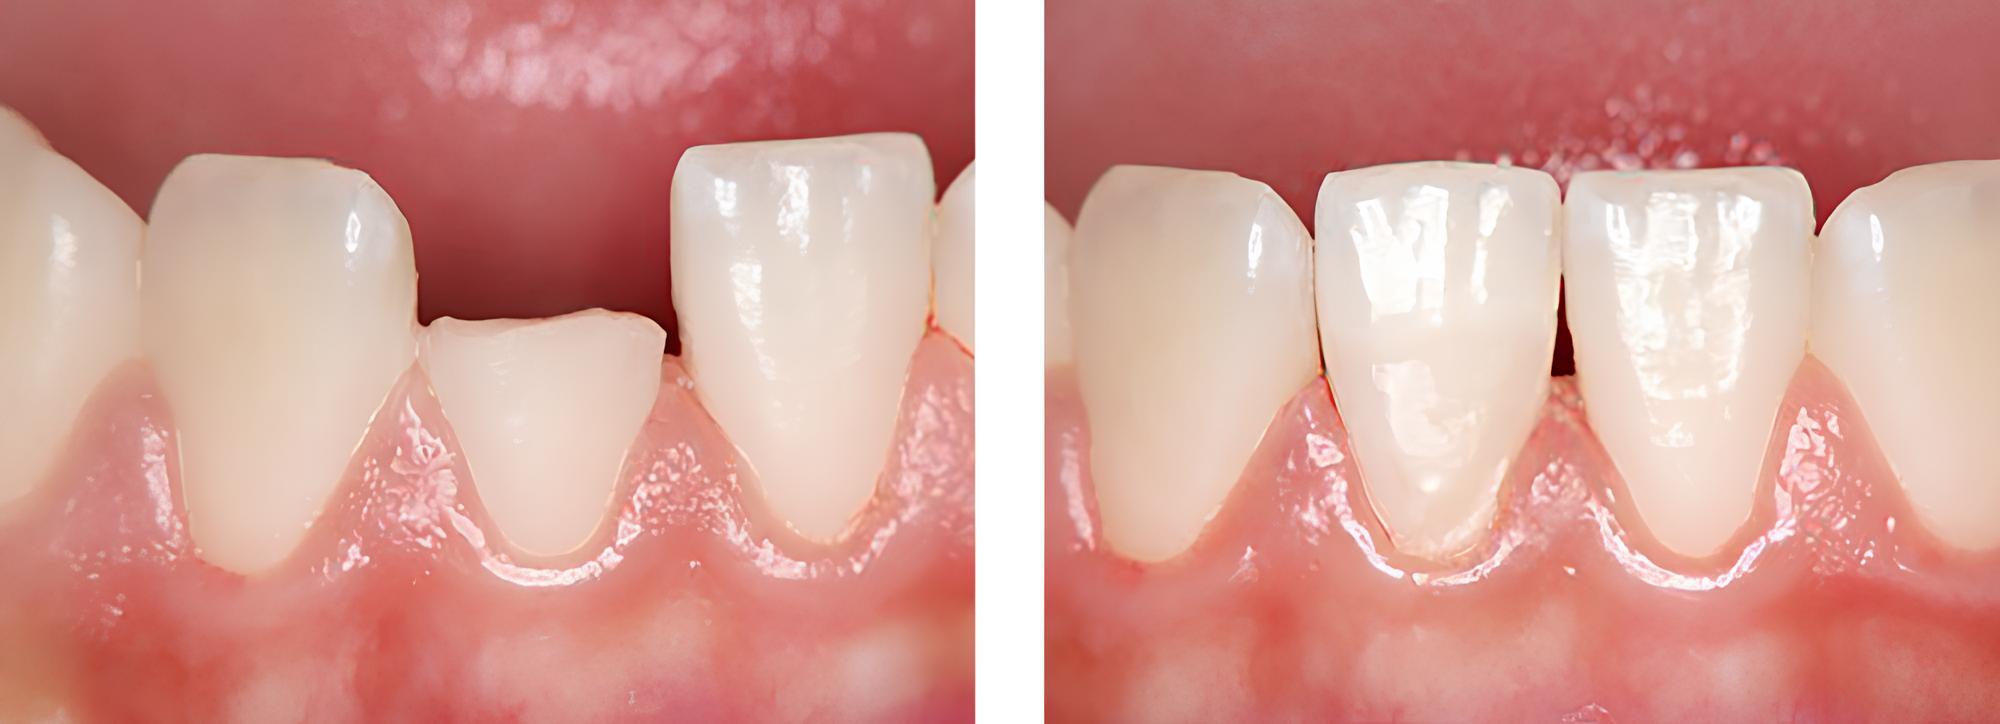

小児歯科

術前

術後

| 治療内容 | 外傷による歯冠破折に対してCRにて破折片の再接着を行った |

|---|---|

| 治療期間・回数 | 1日・1回 |

| 費用 | 保険適用となります |